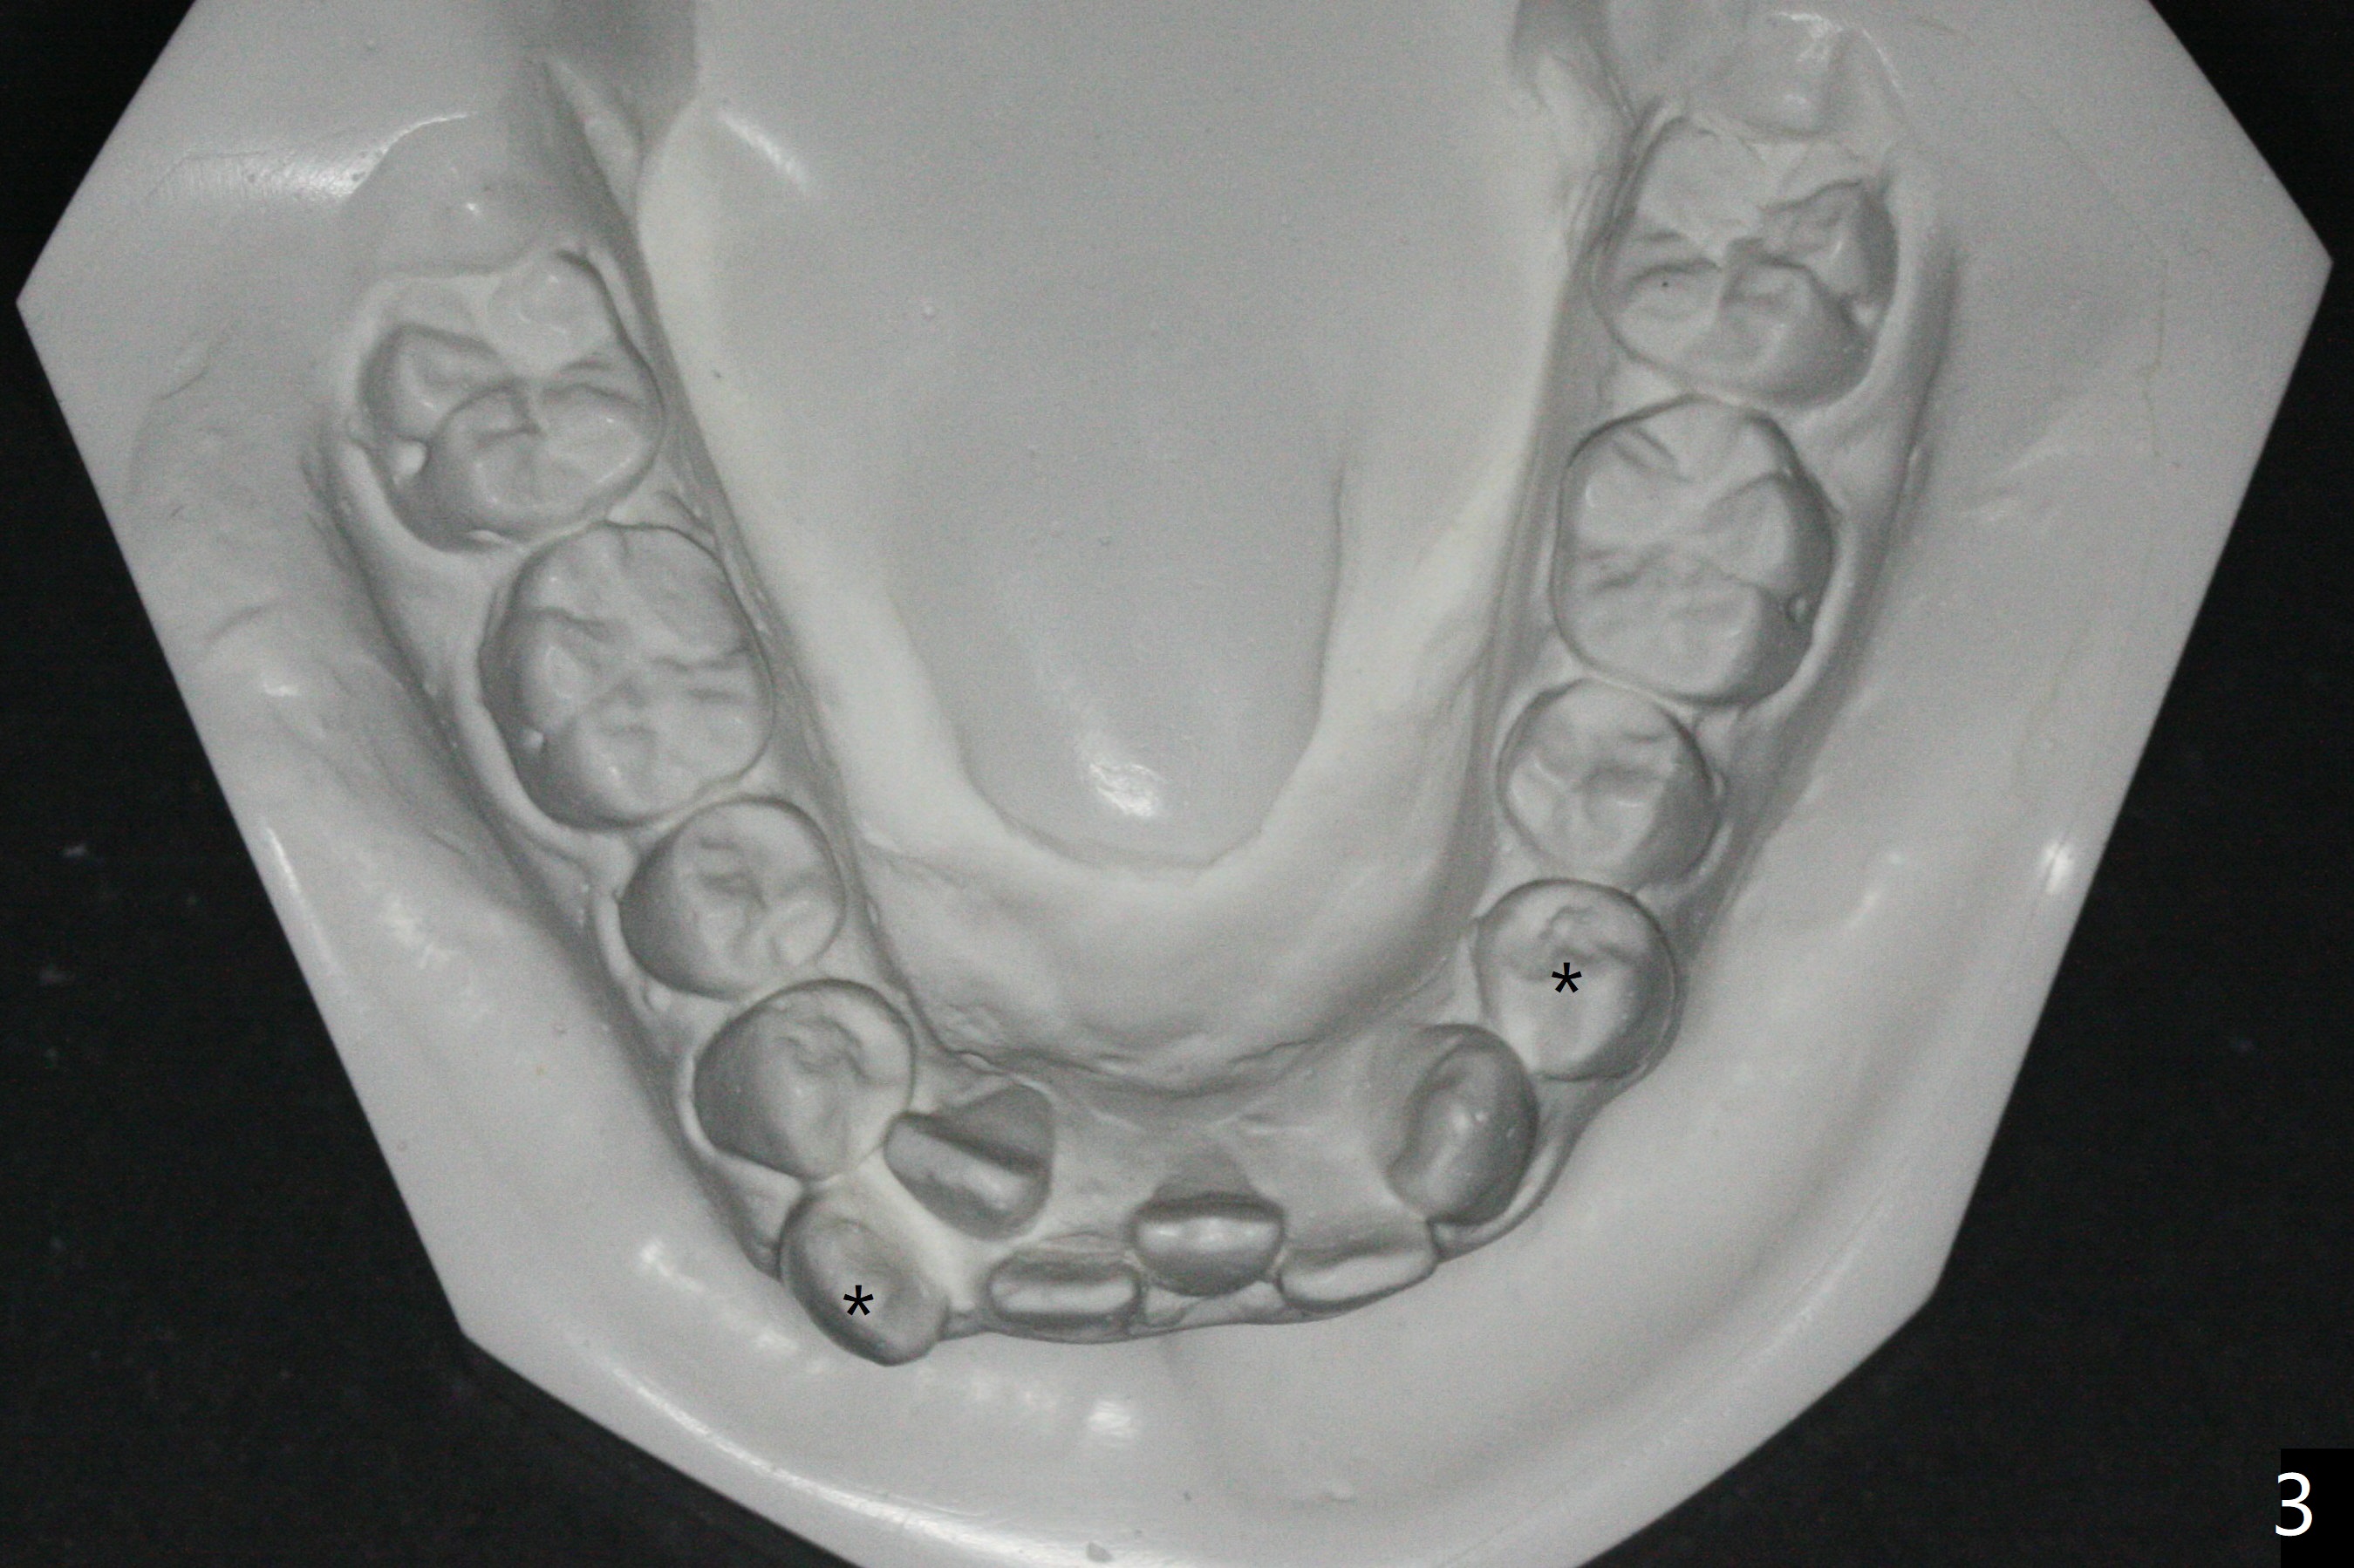

Brackets and Bands will be placed 2 months post extraction (Fig.1-3: *). UR7 (overjet; Fig.1 (7), 2 (arrow)) will be retracted early using LR6 and 7 as anchorages. Because of good posterior interdigitation (Fig.1), U3s and LL3 will be distalized using closed coil spring between 3 and 6 (7 preferrable retrospectively). When this is finished, retract 4 incisors (each arch) together using a posted wire and the same closed spring.

The socket of LR3 heals 2 months post extraction (Fig.4: *). LR4 is bracketed as LR3. Brackets and Bands are placed with 14 niti wires (Fig.5,6).